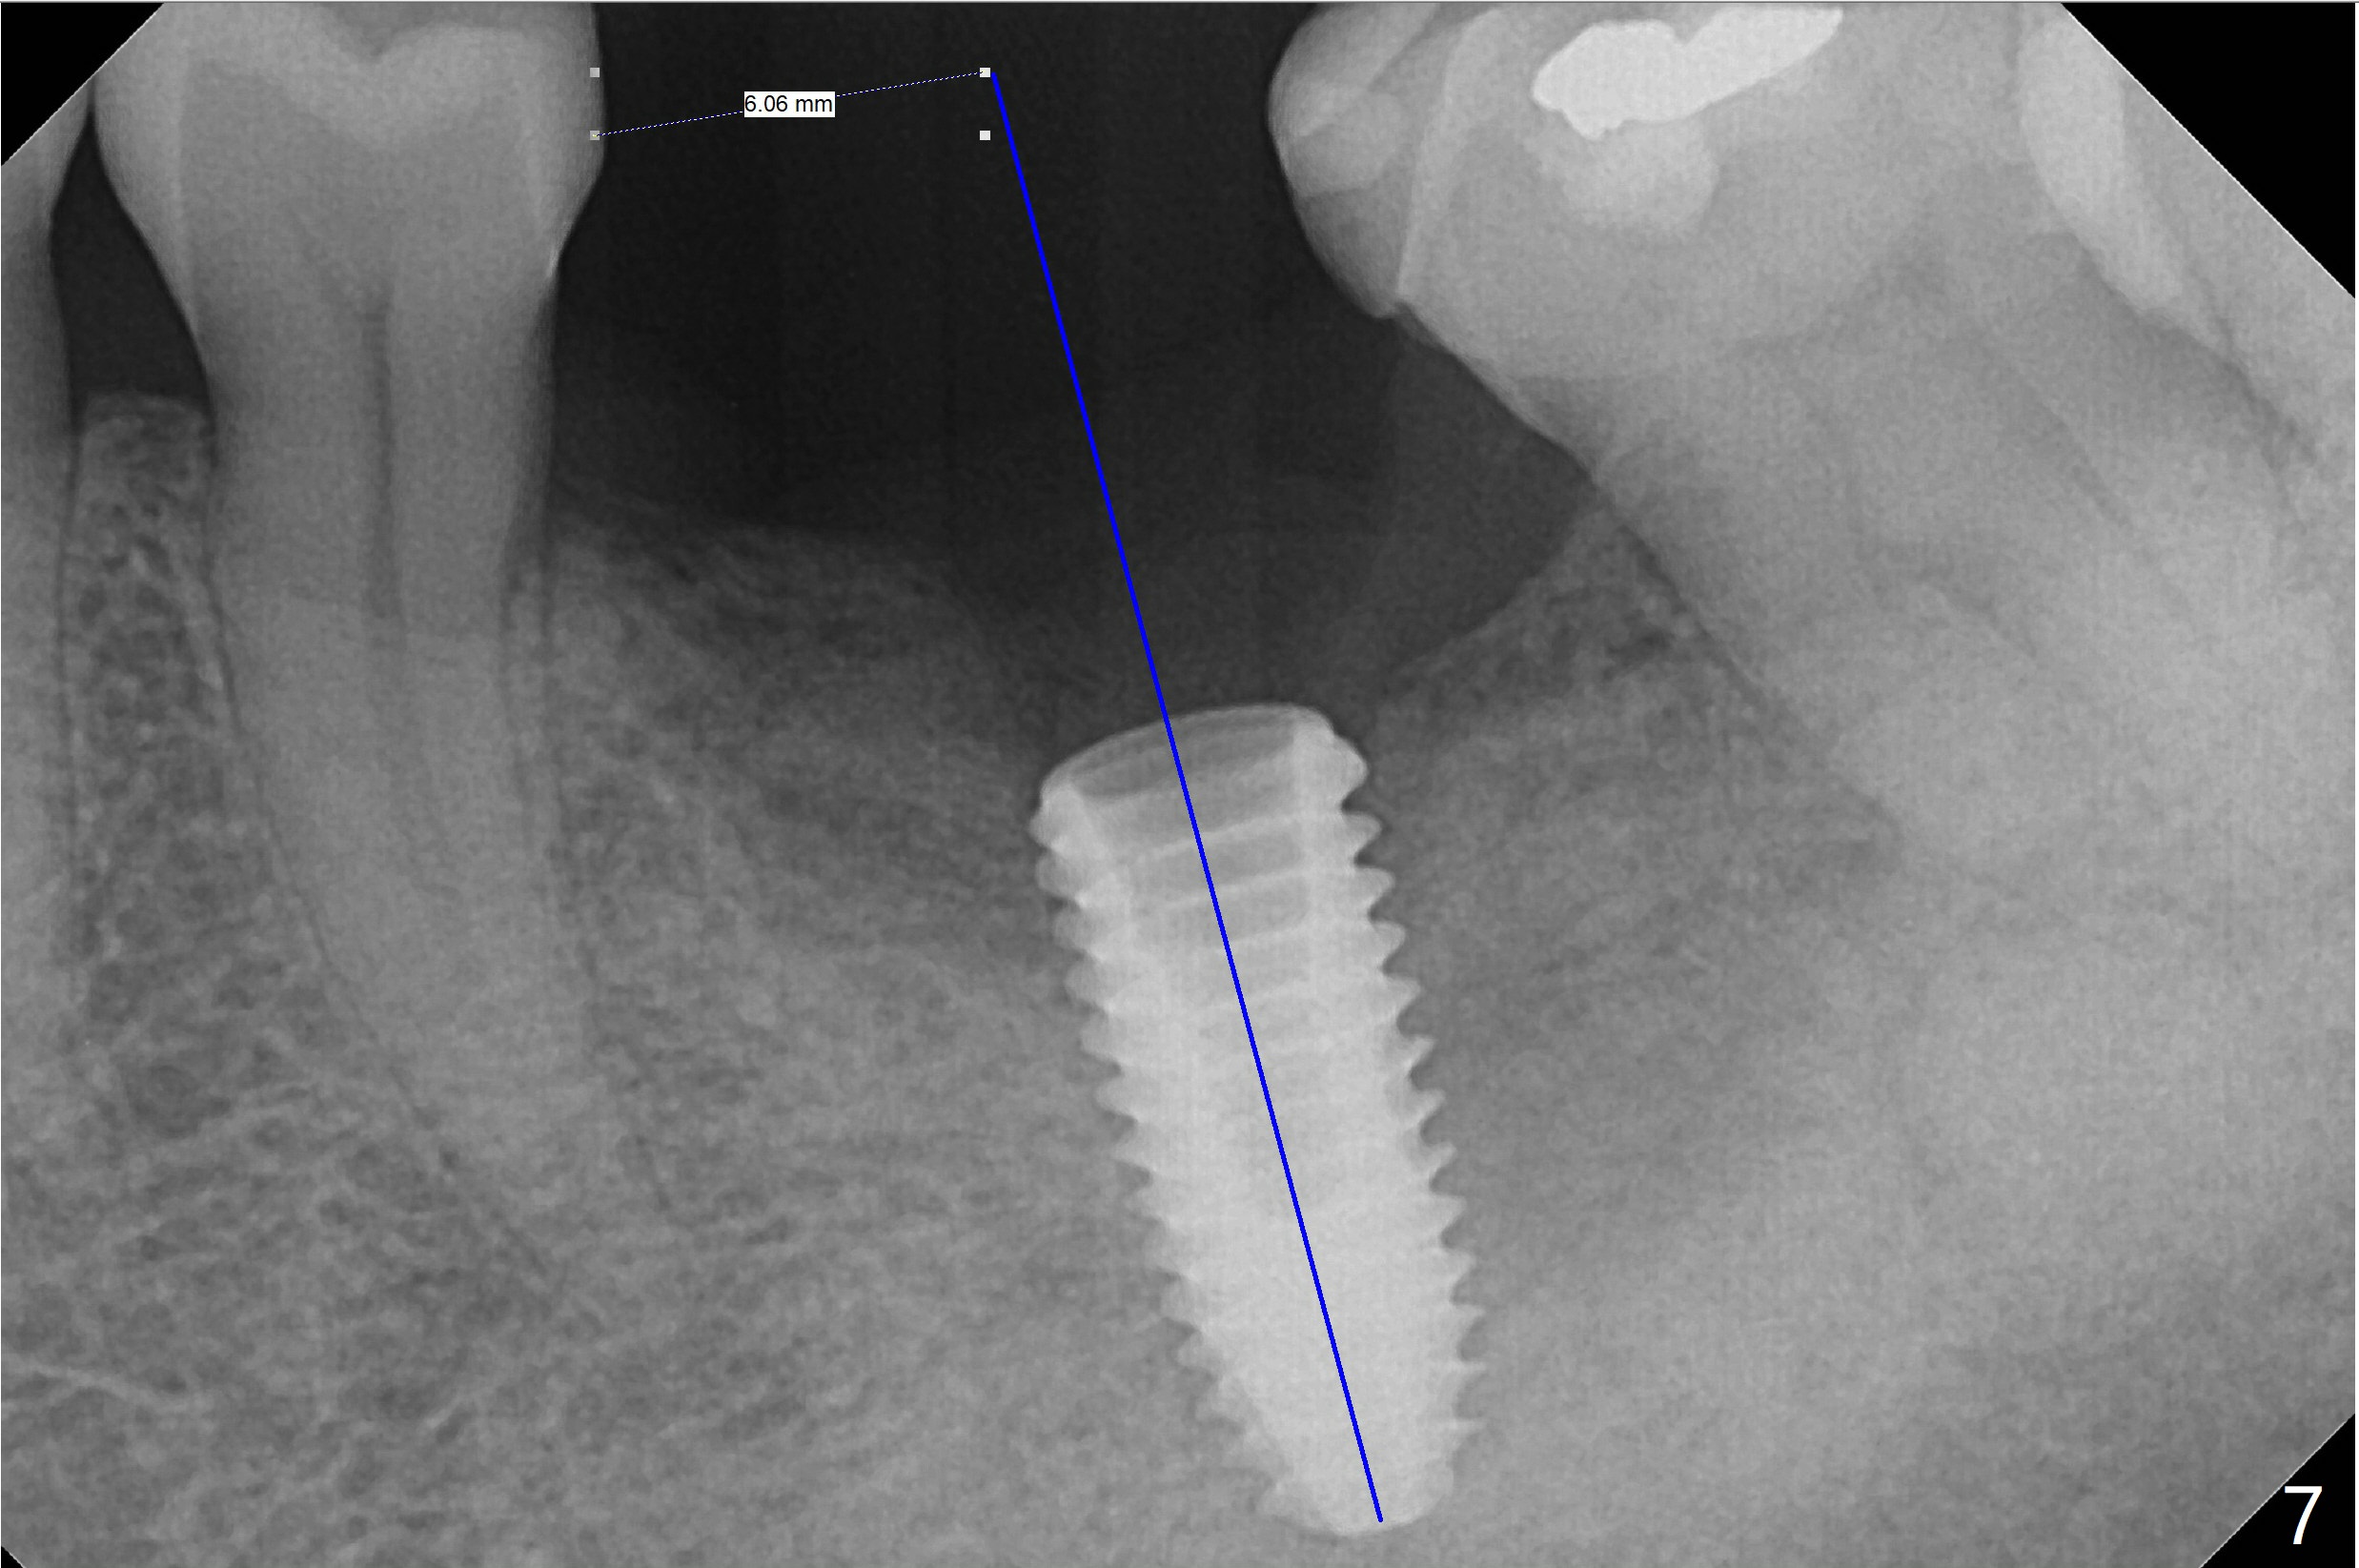

CT taken 4-5 months post extraction shows the outline of the socket at #19 (Fig.1 pink and red dashed line). By the time of surgery (6-7 months post extraction), the ridge looks narrow (Fig.2). In fact the socket does not heal (Fig.3). Osteotomy starts at the mesial border of the socket (Fig.4). When a 5x10 mm dummy implant is placed, the axis begins to be tilted distally (Fig.5 red line), which is more obvious when a definitive longer implant (5x11.5 mm) is placed (Fig.6,7). Osteotomy (Fig.1 arrow) at the mesial slope of the socket (red dashed line) should be initiated more mesial to compensate for the distal drifting while osteotomy is being increased and the implant is being placed. The distal defect is filled with Vanilla graft. Probably due to the mesial slope and the distal defect, the primary stability is <10 Ncm. A healing screw is placed with Vanilla allograft/autogenous bone. The bone forms coronal to the implant 4 months postop (Fig.8 *), which is removed for uncover. The mesial gingival embrasure of the permanent crown is large (Fig.9 *), as related to the mesial undercut associated with a 5.7x4 mm A 15 degree angled abutment (Fig.10). Reduction in the undercut should be able to help lab decrease the gingival embrasure (Fig.11 red line). The bone density around the implant increases with distinct trabecular pattern consistent with stress 5 months post cementation (1 year postop, Fig.12).